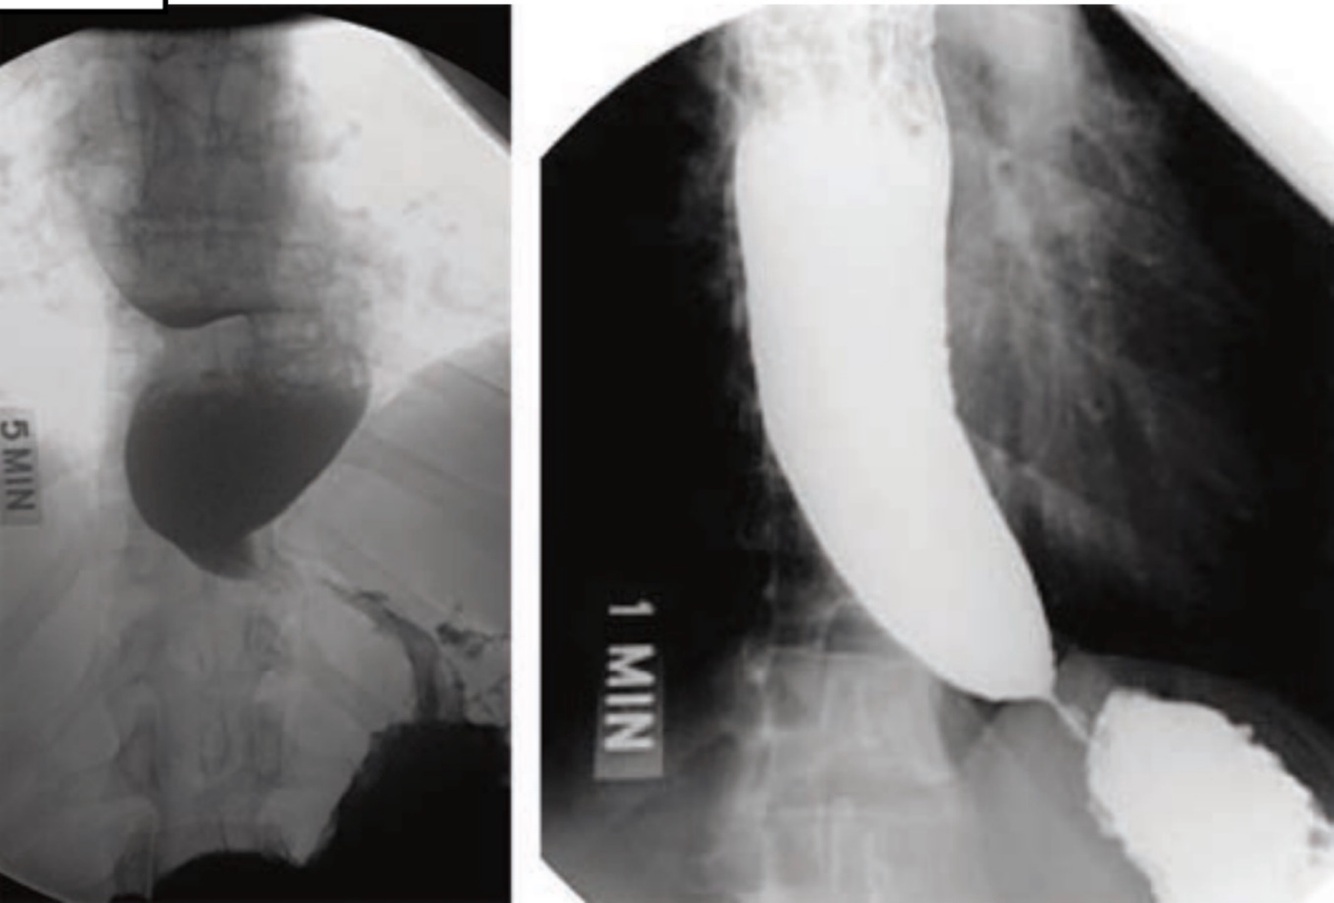

barium swallow x-ray of achalasia

dilated esophagus with poor emptying, an airfluid level, and tapering at the LES giving it a beak-like appearance